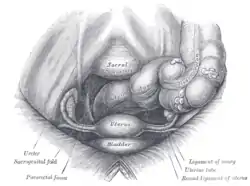

Fetus in utero, between fifth and sixth months. Female pelvis and its contents, seen from above and in front

Female pelvis and its contents, seen from above and in front The arteries of the internal organs of generation of the female, seen from behind